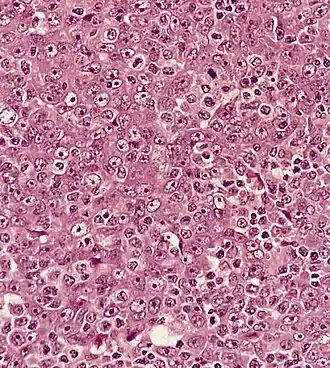

Gemetastaseerd nasofarynxcarcinoom in een lymfeknoop